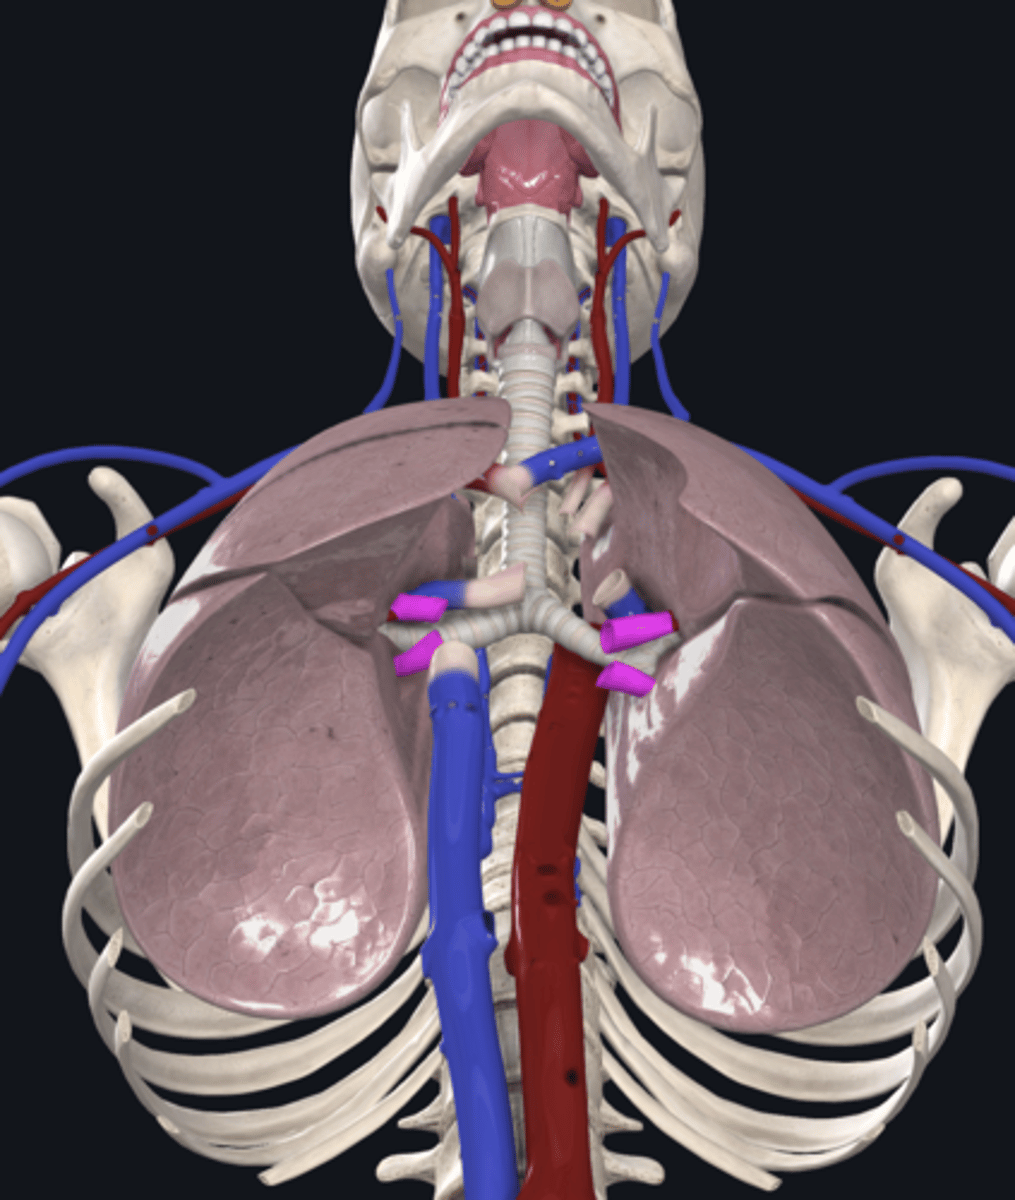

right lung

superior lobe of right lung

middle lobe of right lung

inferior lobe of right lung

left lung

superior lobe of left lung

inferior lobe of left lung

pulmonary artery

pulmonary vein

hilum of right lung

hilum of left lung

right main bronchus

left main bronchus

lobar bronchi

terminal bronchi